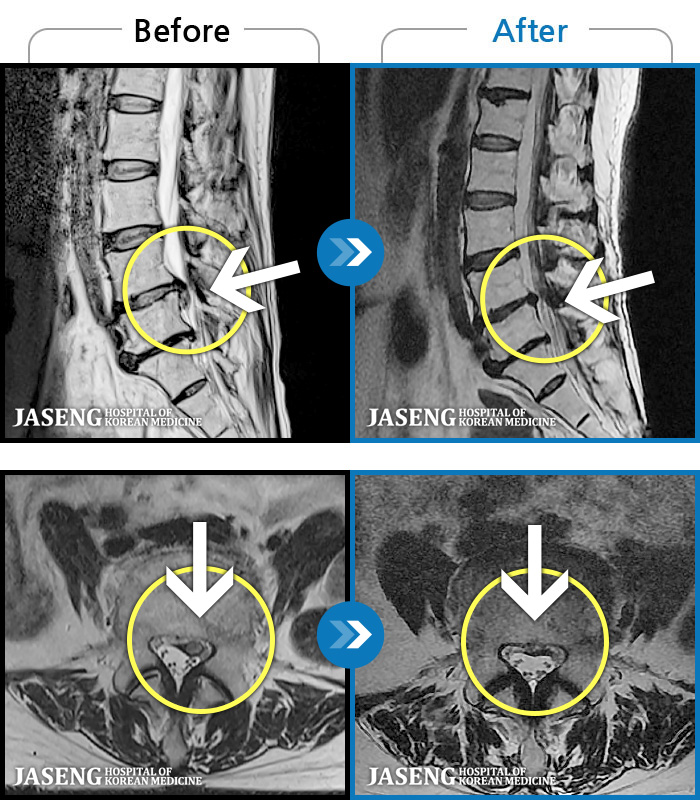

MRI ġ

1,304 MRI ũ ʸ Ȯϼ.